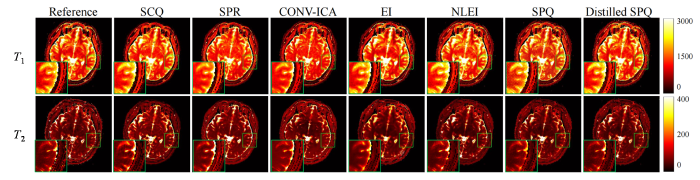

尽管将1 000长实采活体数据重建的定量参数图直接作为伪标签监督训练可能会引入学习偏差,但仍可以将其作为参考图像Reference,辅助对实采活体数据实验结果的定性判断.图8 与图9 分别展示了基于两组200长度实采活体测试数据的不同方法参数量化结果对比.实验结果表明,本文提出的Distilled SPQ方法以及另一种自监督参数量化方法NLEI,在量化结果中所呈现的组织边缘细节与参考图像Reference最为一致.由于这两种方法均引入了基于布洛赫方程的指纹信号生成过程,结果进一步验证了在参数量化过程中融入物理模型先验的有效性.

图8

基于一组200长度实采活体测试数据的不同方法参数量化结果对比

Fig. 8

Comparison of parameter quantification results of different methods based on a set of 200 lengths of in vivo test data

图9

基于另一组200长度实采活体测试数据的不同方法参数量化结果对比

Fig. 9